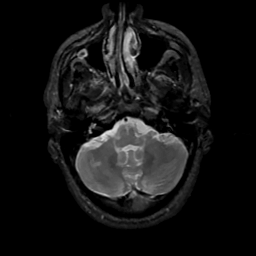

MR Study #6, March 17, 1991 -- Slice #10

[Home][Help][Clinical][Tour 1][Tour 2] Slice 10